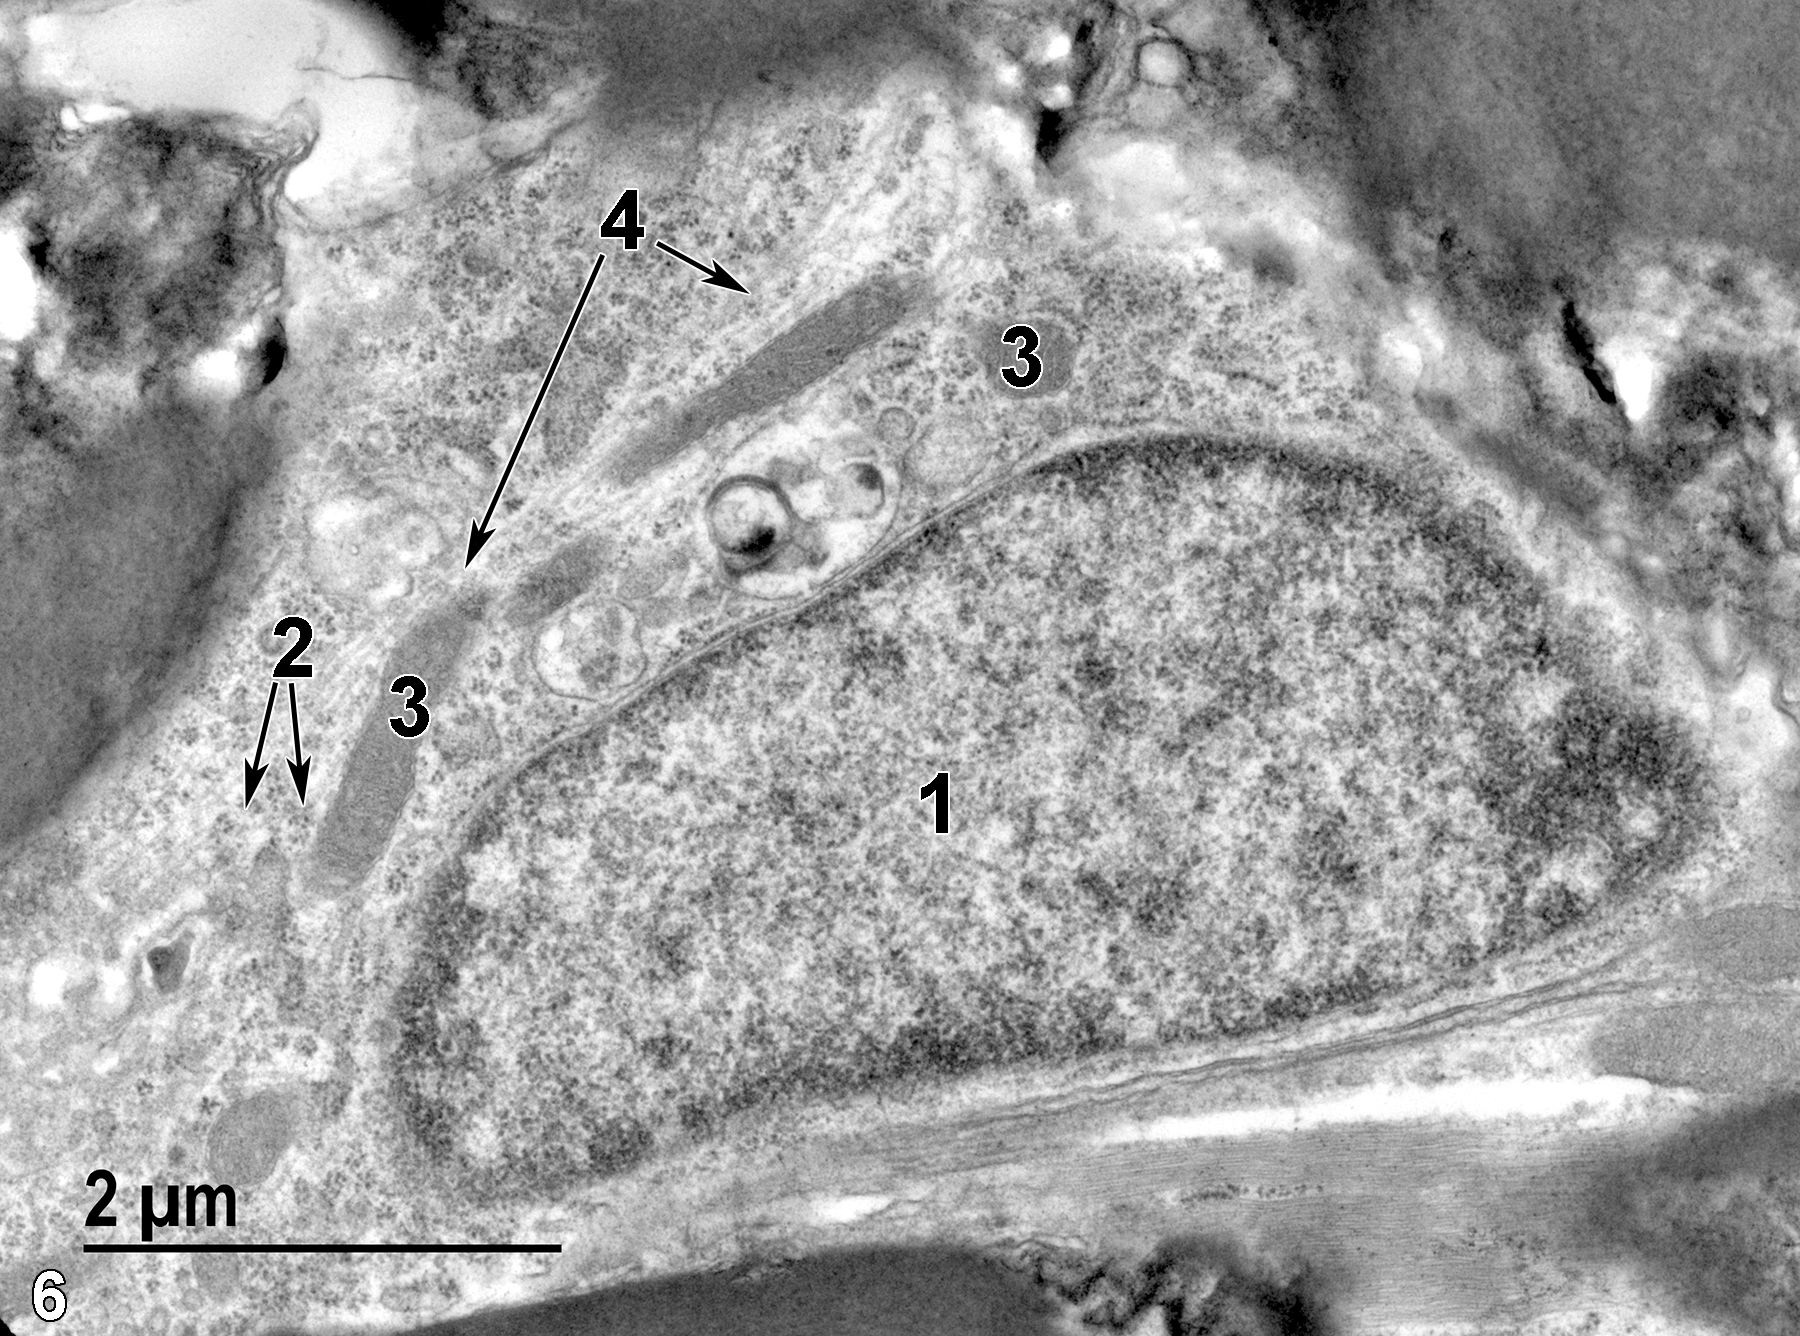

The spinal cord has a central canal with a butterfly-shaped gray matter area surrounded by white matter. There are three layers of connective tissue (meninges) surrounding the outer aspect of the white matter, starting from the innermost layer: pia mater, arachnoid, and dura mater. Gray matter of the brain and spinal cord consists of numerous nerve cells (perikaryon, nucleus, and dendrites), whereas the nerve fibers (axons) predominate in white matter. The perikarya are large polyhedral cells with central nuclei that have prominent nucleoli and little heterochromatin. They have abundant rough endoplasmic reticulum cisternae and large numbers of free ribosomes and intermediate filaments. In addition to the nerve cells, blood vessels and several types of microglial cells are found in both the white and gray matter of the spinal cord. Oligodendrocytes have fewer cytoplasmic processes than astrocytes and are often aligned in rows between axons. They have spherical nuclei and electron-dense cytoplasm with many microtubules, rough endoplasmic reticulum, and mitochondria. They produce myelin that surrounds myelinated axons. Astrocytes are the largest microglial cells, with large centrally located nuclei that lack nucleoli. Astrocytes provide structural support, supply energy, are involved in inflammatory responses, and are phagocytic. Protoplasmic astrocytes are found in gray matter and have numerous short branching cytoplasmic processes, whereas fibrous astrocytes are more common in white matter and have fewer, narrower, and straighter cytoplasmic processes than those found in protoplasmic astrocytes.